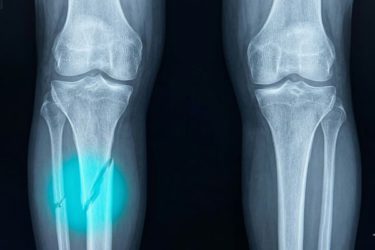

খেলাধুলা বা দৌড়ঝাঁপ করতে গিয়ে হাড় ভাঙার ঘটনা নতুন কিছু নয়, বিশেষ করে শিশু-কিশোরদের ক্ষেত্রে। এমন পরিস্থিতিতে সাধারণত প্লাস্টার, অস্ত্রোপচার কিংবা দীর্ঘদিন বিশ্রামে থাকতে হয়। অনেক সময় হাড় ঠিকভাবে জোড়া লাগাতে ধাতব স্ক্রু বা প্লেটও ব্যবহার করা হয়, যা রোগীর জন্য কষ্টকর এবং সময়সাপেক্ষ।

খেলাধুলা বা দৌড়ঝাঁপ করতে গিয়ে হাড় ভাঙার ঘটনা নতুন কিছু নয়, বিশেষ করে শিশু-কিশোরদের ক্ষেত্রে। এমন পরিস্থিতিতে সাধারণত প্লাস্টার, অস্ত্রোপচার কিংবা দীর্ঘদিন বিশ্রামে থাকতে হয়। অনেক সময় হাড় ঠিকভাবে জোড়া লাগাতে ধাতব স্ক্রু বা প্লেটও ব্যবহার করা হয়, যা রোগীর জন্য কষ্টকর এবং সময়সাপেক্ষ।

তবে চিকিৎসাবিজ্ঞানে এসেছে এক অভিনব প্রযুক্তি, যা এই প্রক্রিয়াকে অনেক সহজ করে দিতে পারে।

অস্ট্রেলিয়ার গবেষকেরা উদ্ভাবন করেছেন এক ধরনের বিশেষ জৈব আঠা, যা হাড় জোড়া লাগাতে ব্যবহার করা যায়। এই আঠা প্রয়োগের জন্য তৈরি করা হয়েছে একটি থ্রি-ডি প্রিন্টিং কলমের মতো যন্ত্র, যা দেখতে অনেকটা গ্লু গানের মতো।

চিকিৎসকেরা এই কলমের মাধ্যমে ভাঙা হাড়ের স্থানে বিশেষ ধরনের জেল প্রয়োগ করেন। এরপর সেখানে নির্দিষ্ট আলো বা অতিবেগুনি রশ্মি প্রয়োগ করলে আঠাটি দ্রুত শক্ত হয়ে যায় এবং হাড়ের মতোই মজবুত কাঠামো তৈরি করে।

এই প্রযুক্তির নাম দেওয়া হয়েছে “বায়োপেন”। এর সবচেয়ে বড় সুবিধা হলো—হাড় দ্রুত জোড়া লাগতে পারে এবং রোগীকে দীর্ঘদিন প্লাস্টার নিয়ে থাকতে হয় না। এমনকি অপারেশনের সময়ই চিকিৎসকেরা নির্ভুলভাবে হাড় ঠিক করে দিতে পারেন।

বিশেষজ্ঞদের মতে, এই প্রযুক্তি ভবিষ্যতে হাড়ের চিকিৎসায় বড় পরিবর্তন আনতে পারে। হয়তো এমন এক সময় আসবে, যখন প্লাস্টার করা হবে অতীতের বিষয়।